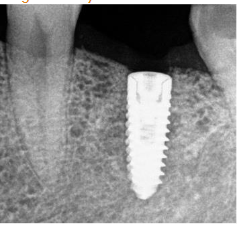

After a period of 5-month showing intraorally and radiographically the site from where bone core using trephine was taken for histological analysis; the same site where implant, Mis implant 3.75/11.5 was placed.